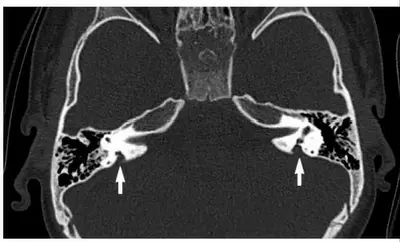

大前庭水管

耳蜗与前庭相连,其中内淋巴囊通过内淋巴管与前庭相连。正常情况下,内淋巴管直径1mm左右,发育异常会成为大前庭水管。CT表现为裂隙状黑影,亦有人称为喇叭口样改变。听力学表现为波动性听力下降,例如上呼吸道感染、头部碰撞等会引起听力下降,最终下降至无法满足日常学习和生活,其人工耳蜗植入效果较好。